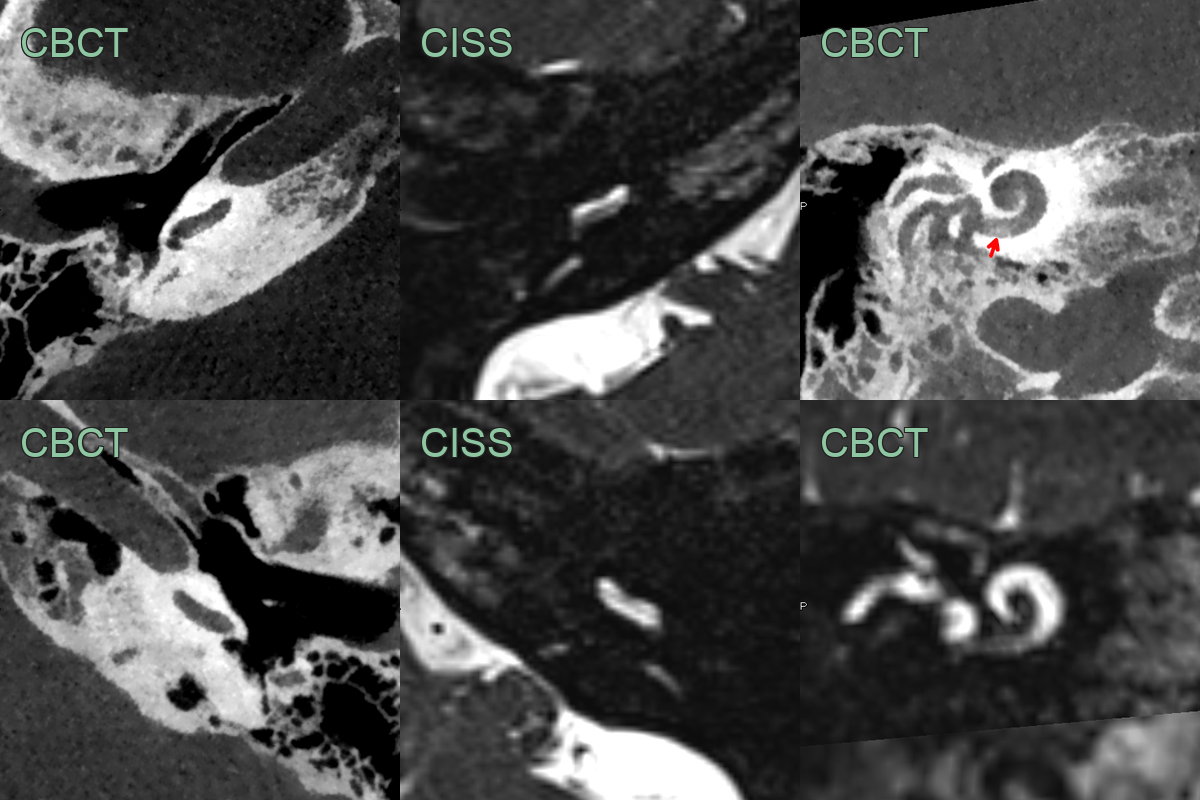

Labyrinthitis ossificans

- 50-year-old patient presented with progressive right sided sensorineural hearing loss.